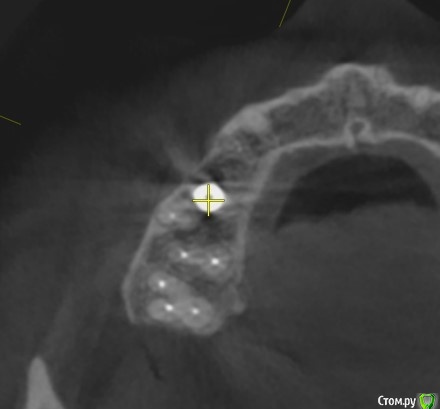

Tatiana72 Опубликовано 27 октября, 2020 Автор Поделиться Опубликовано 27 октября, 2020 Добрый вечер!Выкладываю скрины срезов Ссылка на исследованиеhttps://yadi.sk/d/ViQR0U6R2QjHzg Ссылка на комментарий

Дмитрий М Опубликовано 28 октября, 2020 Поделиться Опубликовано 28 октября, 2020 Добрый вечер!Выкладываю скрины срезовImage4.jpgImage5.jpgImage9.jpg Ссылка на исследованиеhttps://yadi.sk/d/ViQR0U6R2QjHzg не волнуйтесь всё хорошо, по КТ корень зуба не задетесть небольшой очаг разряжения на одном из апексов, обратитесь к стоматологу 1 Ссылка на комментарий